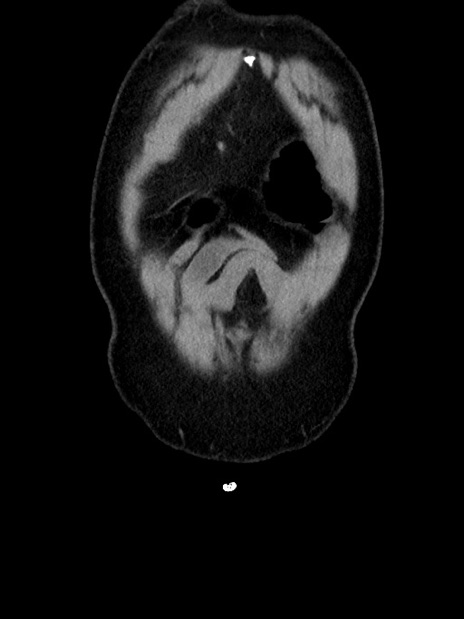

横断像

【症例】70歳代 男性

【主訴】腹部膨満、嘔吐

【現病歴】昨日より腹部膨満感出現。本日増悪し、仙痛出現。嘔吐あり、受診。

【既往歴】糖尿病、胆摘後

【身体所見】BP 149/80mmHg、HR 74/min、BT 35.9℃、腹部:膨満、軟、圧痛なし。腸雑音減弱あり。上腹部正中切開瘢痕あり。

【データ】WBC 13500、CRP 1.72